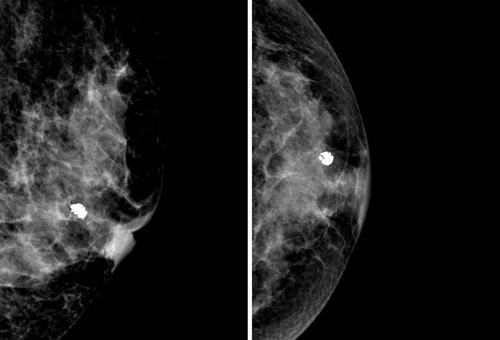

一般來說,若鈣化點比較大顆,沒有群聚簇集的特性,形狀外觀的界線清楚明確,長的均勻、對稱,就屬于良性鈣化點的特征。

乳房的鈣化點大部分都是良性的,或伴有其他良性病變,如乳腺增生。所以,乳房鉬靶上如果看到大大的白點,通常就是良性鈣化點,如纖維腺瘤就常常會在鉬靶的影像上出現(xiàn)爆米花狀的粗糙大白點。